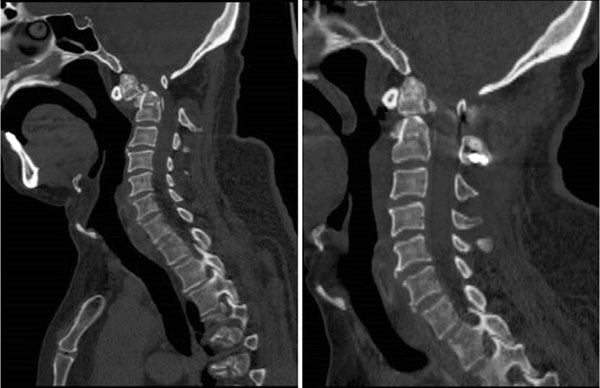

术前术后CT对比